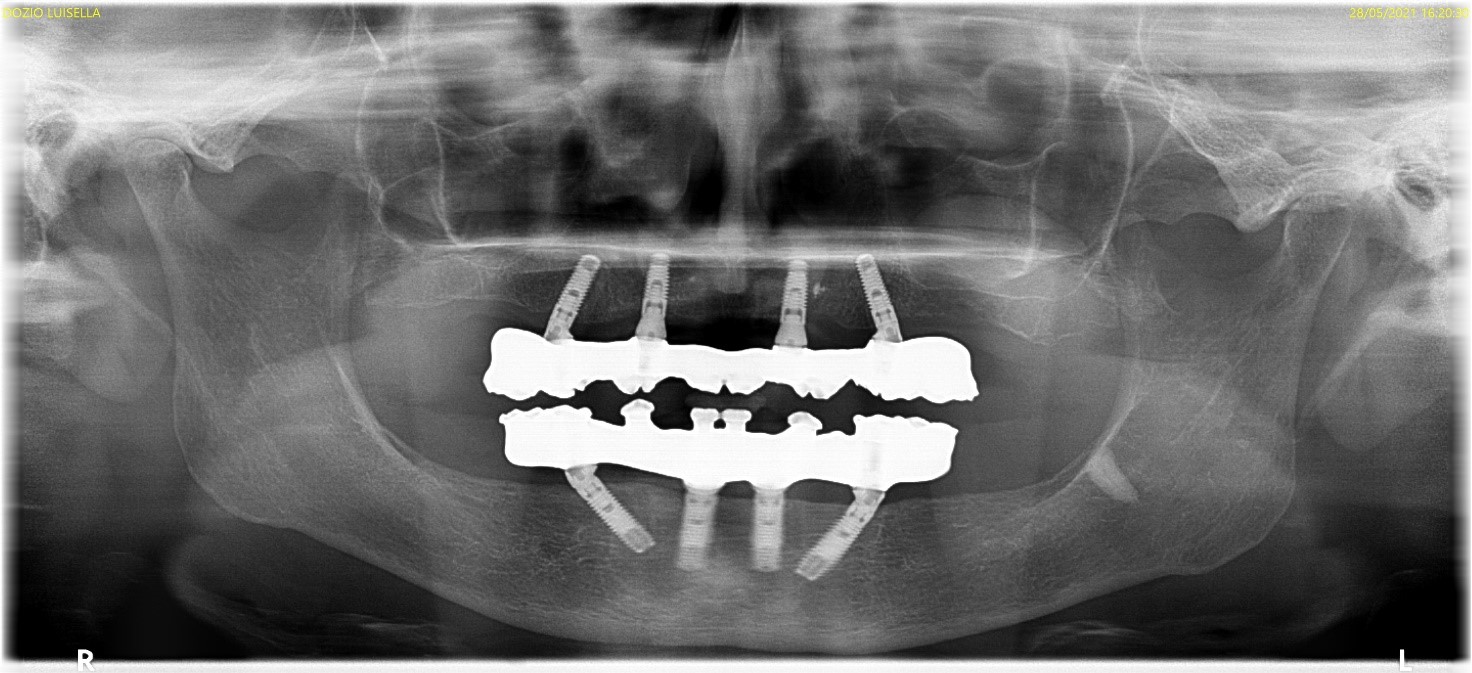

Paziente di sesso femminile si presenta in studio con parziale edentulia superiore e inferiore. Nell’arcata superiore sono presenti residui radicolari degli elementi 11, 13, 16 e ponte incongruo da 24 a 26. Nell’arcata inferiore l’edentulia è posteriore e sono presenti elementi da 33 a 43 e residuo radicolare di 34.

foto 00 ortopantomografia sit pre chirurgica

Il giorno dell’intervento, si procede alla bonifica superiore e inferiore. Successivamente, superiormente sono stati inseriti di 2 impianti inclinati distalmente in zona 25 e 15 (misura 3.7*11.5) e 2 impianti posizionati ortogonali alla cresta ossea in zona 22 e 12 (misura 3.7*10). Inferiormente sono stati inseriti 2 impianti inclinati distalmente in zona 44 e 34 (misura 3.7*13) e 2 impianti posizionati ortogonali alla cresta ossea in zona 32 e 42 (misura 3.7*13). Coppia di inserimento degli otto impianti non superava i 25Ncm. Sono dunque state posizionate viti di copertura e, suturati i lembi con sutura riassorbibile 5/0, sono state consegnate le protesi totali provvisorie e la paziente è stata dimessa.

foto 19b ortopantomografia verificatore